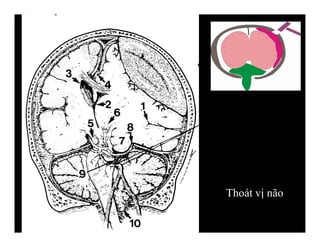

THOÁT VỊ NÃO

-Thoát vị dưới liềm: hồi đai

qua dưới bờ tự do liềm não

Đường giữa lệch.

-Ép não thất cùng bên

-Có thể rộng não thất đối bên

-Nhồi máu động mạch não

trước

THOÁT VỊ DƯỚI LIỀM NÃO

-Mỏm móc của hồi

cạnh hải mã thoát

vị qua khe lều tiểu

não xuống dưới

+Xoá bể trên yên

+Rộng bể góc cầu

tiểu não cùng bên

THOÁT VỊ XUYÊN LỀU HƯỚNG XUỐNG